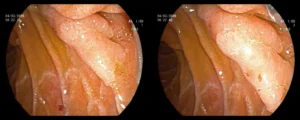

Πολύποδας δωδεκαδακτύλου

![]()